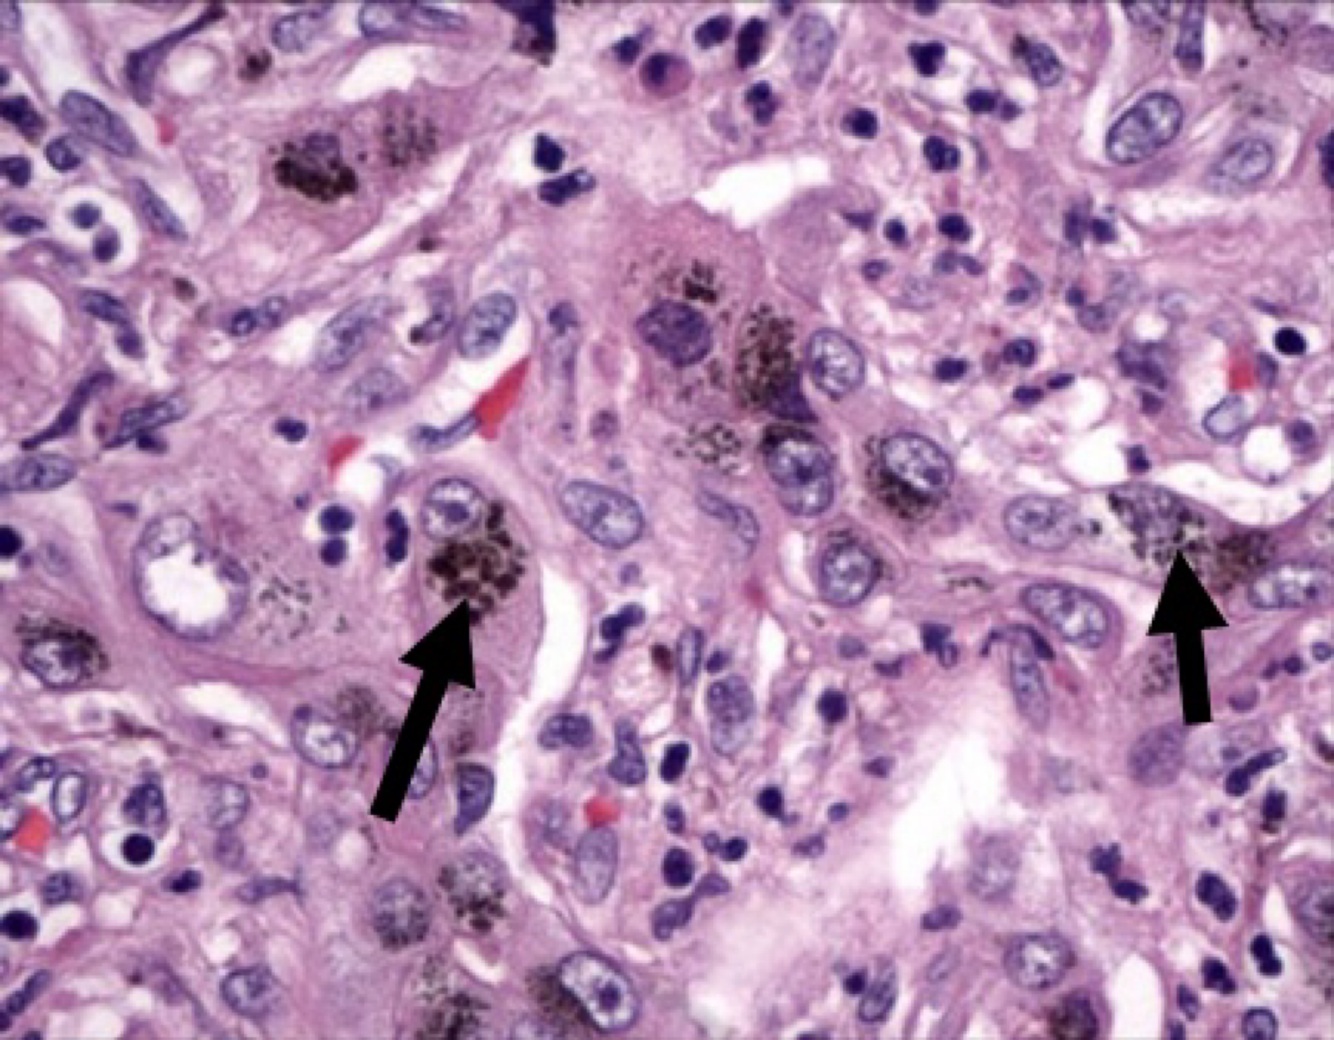

Hemochromatosis :hemosiderin-laden hepatocytes and Kupffer cells